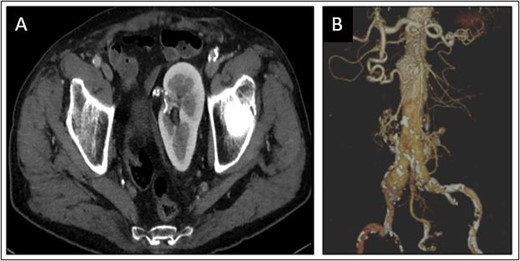

An 81-year-old man was incidentally diagnosed with AAA during a routine abdominal echography. His risk factors included active smoking and hypertension. Computed tomography scan confirmed the presence of an aorto-iliac aneurysm and a CSPK (Fig. 1A) supplied from a solitary renal artery arising from the aortic bifurcation (Fig. 1B).

Congenital solitary pelvic kidney (A), aortic carrefour and single renal artery (B).